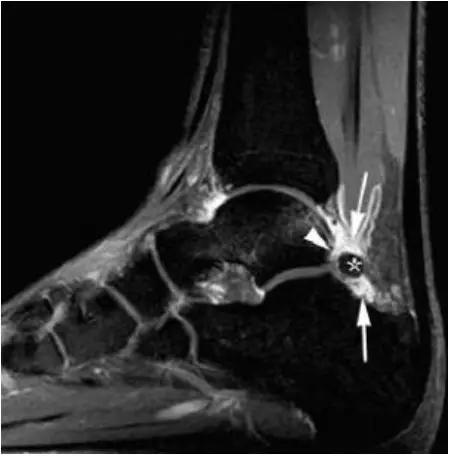

- MRI 检查示距后三角骨及周围软组织有水肿信号,距后三角骨和距骨之间正常的低信号纤维连接中断,出现液性信号。

3、MR表现:

- 三角籽骨或距骨后三角结构模糊和变形,T1WI信号降低, T2WI信号升高,

- 周围脂肪水肿,

- 踇趾长屈肌腱信号升高,见鞘膜积液,

- 胫骨后下跟骨上缘骨结构形态变化和信号异常,

- 三角籽骨和距骨退行性囊变。

三角籽骨综合征

三角籽骨综合征并跟腱滑囊积液